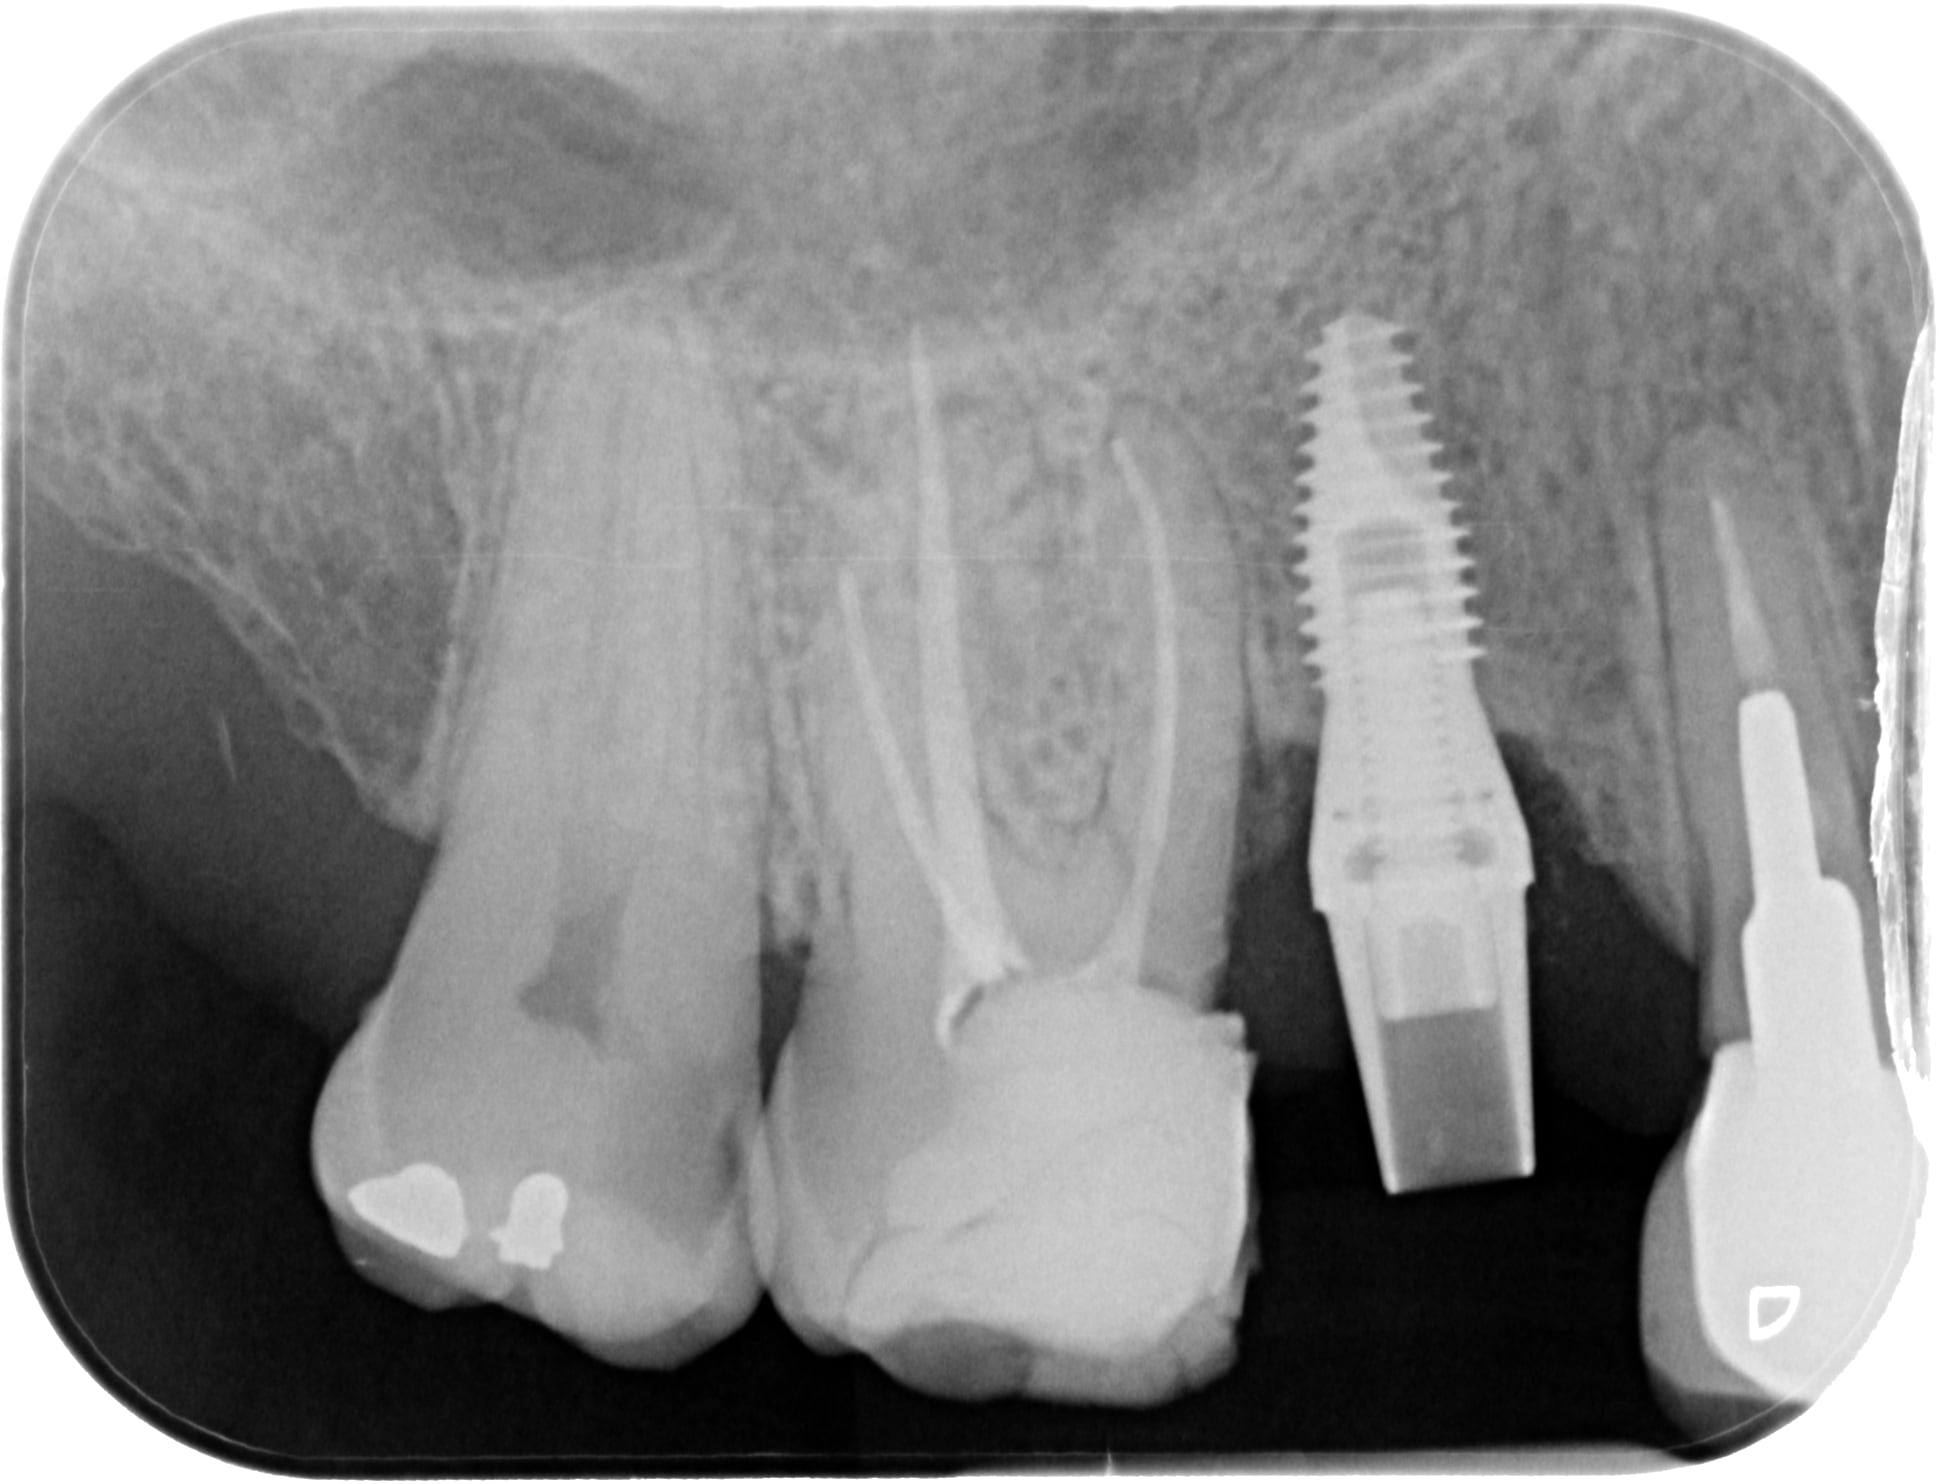

Identification implant

Patient que je vois pour la premiere fois. Il a posé les implants en Argentine(il est de la-bas)

J aime bien la gestion du point de contact :,-)

bon gros avantage, c'est un hex externe donc tu vas trouver plein de compatibilités....;-)

La pose est curieuse : c'est un tissu ou un bone level ?